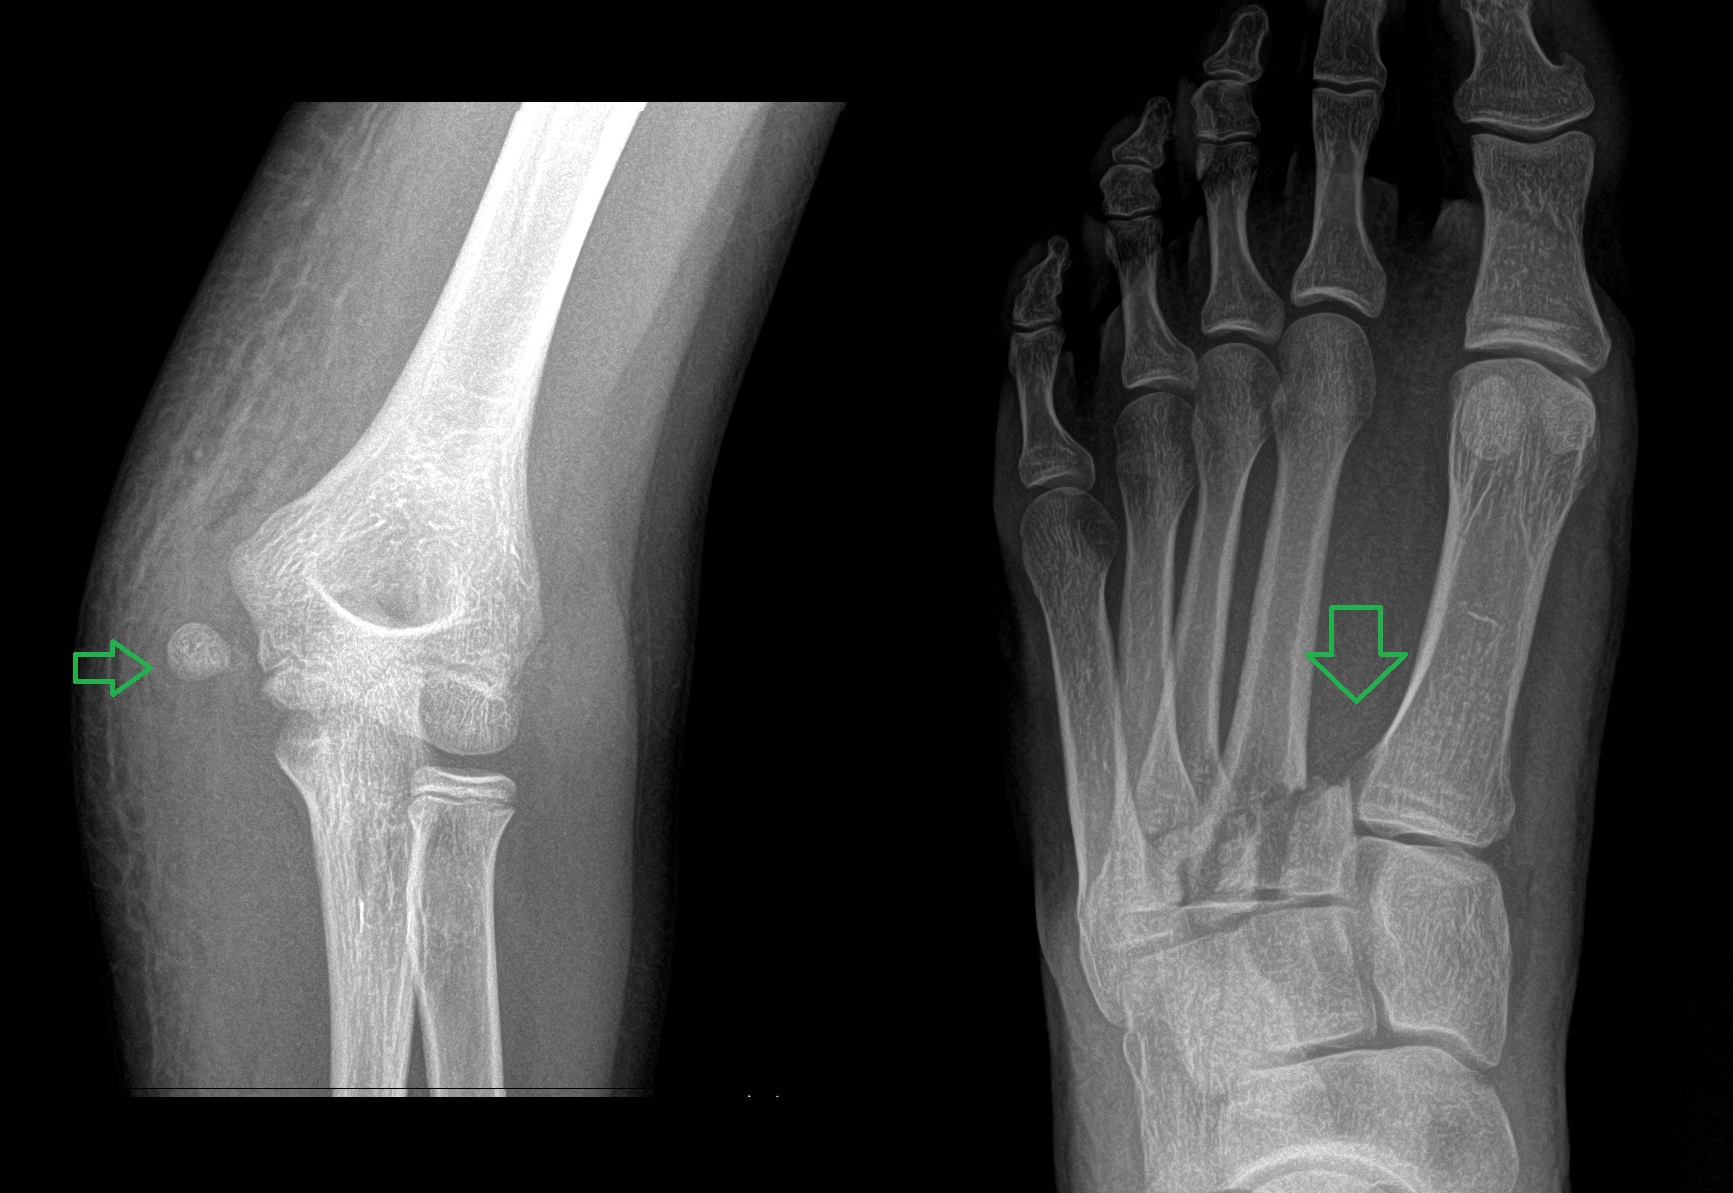

A 21 year old female with left forefoot pain after rolling her foot 2 weeks ago.

base of the 3rd metatarsal fracture